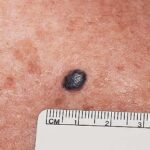

Hemangiomas that are fully formed tumors at the time of birth and do not proliferate in postnatal life are referred to as congenital hemangioma or congenital nonprogressive hemangioma. There are two major sub-types recognized on the basis of their natural history: the rapidly involuting congenital hemangioma (RICH) and non-involuting congenital hemangioma (NICH). Collectively, both are sometimes referred to as congenital nonprogressive hemangioma. The distinguishing pathologic features of these tumors are lobules of capillaries set within densely fibrotic stroma containing hemosiderin deposits, focal lobular thrombosis, and sclerosis.103 They are GLUT-1 negative. Both have similar anatomic sites of predilection, such as the extremities or postauricular skin, but they can occur elsewhere. RICH often appears as a raised, violaceous tumor

with large, radiating veins or with overlying telangiectasia and a halo of pallor . Central ulceration may be present. Most RICH involute spontaneously by age 14 months, often sooner, and usually leave residual atrophic inelastic skin in their wake.105